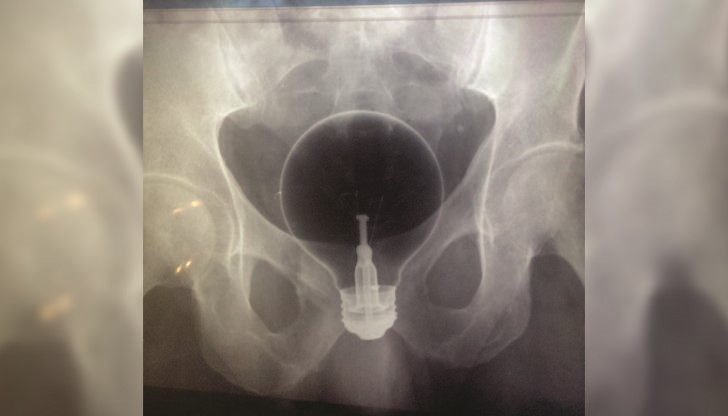

Как идут месячные после рентгена труб - фото презентация